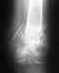

Здравствуйте,у меня был перелом головки пятой пястной кости без смещения,через три недели гипс сняли,наблюдается небольшое отклонение мизинца в сторону ладони,сейчас хожу на физио,хотелось бы узнать останется ли деформация,как развивать руку самостоятельно и какие дальнейшие ограничения.Спасибо,Ольга,25л.